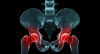

MRI

검사시 특징적인 MRI 소견으로 다른 질환이 없다면 확진할 수 있게 됩니다.

T1 영상에서 산재성의 음영감소 소견(low signal)을 보입니다.

T2 영상에서 산재성의 음영증가 소견(high signal)을 보입니다.